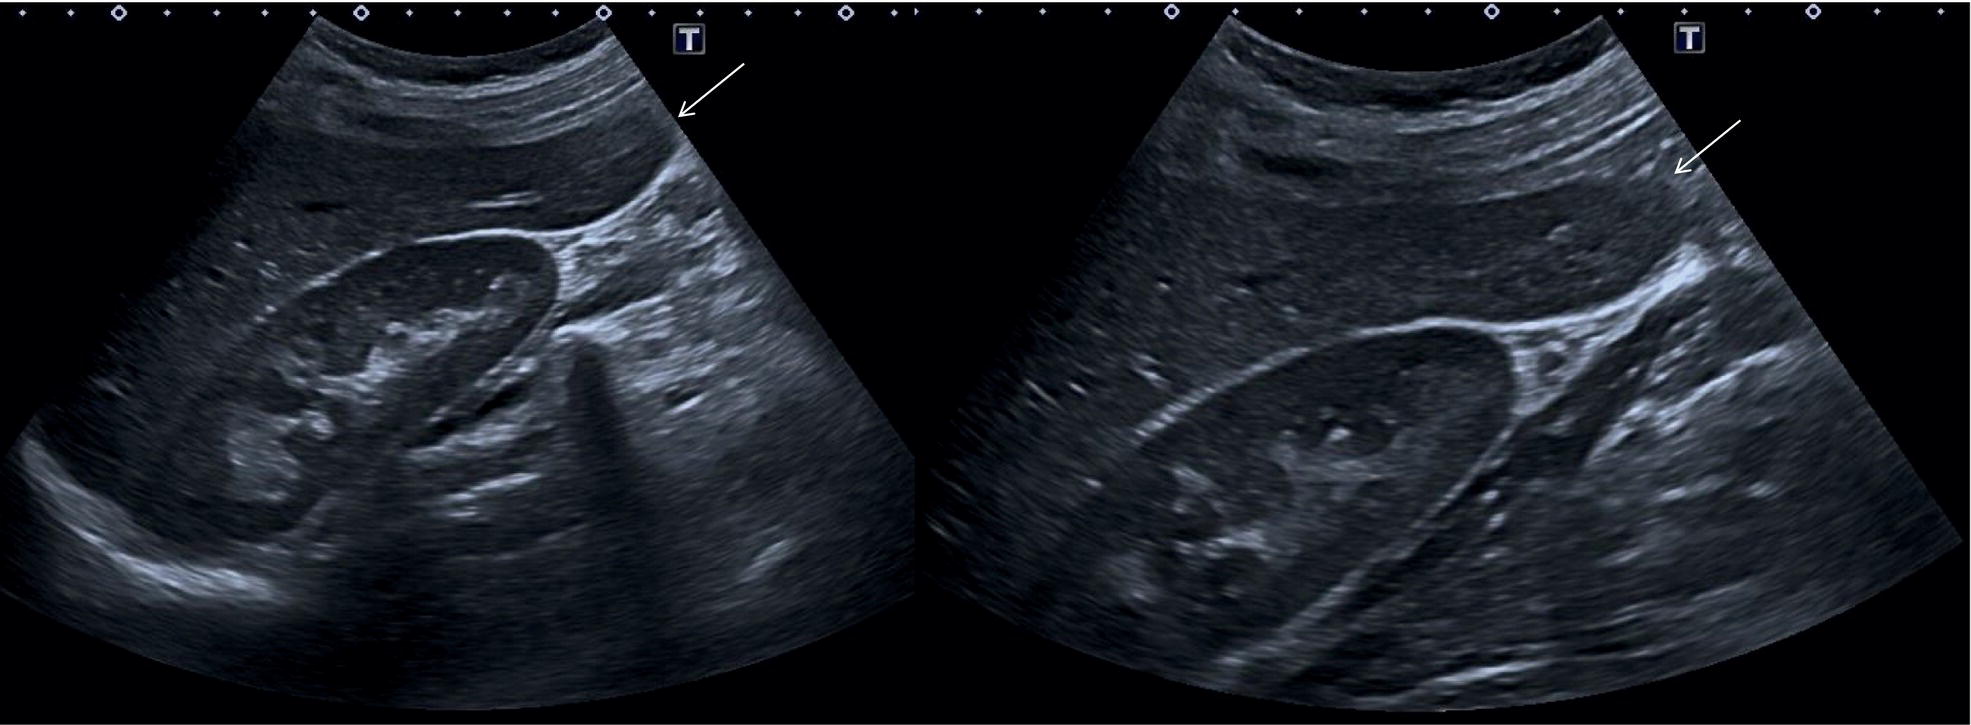

Normal Variants of Liver Anatomy

Liver anatomical variants might be related to the shape, size, and vasculature, as well as the GB and biliary tree. Parenchymal variants include diaphragmatic slips, sliver of liver, Riedel’s lobe, and papillary process of the caudate lobe [5]. Diaphragmatic slips represent incomplete accessory fissures at the site of the diaphragmatic liver surface due to invagination of the diaphragm (Figure 3.16). A sliver of the liver refers to an anatomical variant where the left liver lobe extends to the left hypochondrium, wrapping around part of the spleen (Figure 3.17). Another common variant is a Riedel’s lobe, represented by a downward tongue‐like projection of the lower anterior edge of the right liver lobe (segment VI), sometimes so pronounced as to extend along the right paracolic space up to the iliac fossa (Figure 3.18) [6]. The papillary process is an anterior and medial extension of the caudate lobe, which might resemble a lymph node or mass next to the pancreatic head or IVC (Figure 3.19).